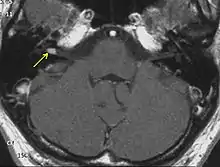

بسبب التقدم الطبي، أصبح لدينا القدرة على تحديد الاورام العصبية السمعية الصغيرة (حتى الأورام المحصورة داخل قناة السمع الداخلية) اختبارات السمع الروتينية قد تكشف عن فقدان السمع والقدرة على تمييز الكلام (المريض قد يسمع الأصوات، ولكن لا يمكنه فهم ما يقال) يجب إجراء تخطيط للسمع لتقييم فعالية السمع في كلتا الأذنين. خسارة السمع في أذن واحدة تدفع الطبيب لاستعمال التصوير بالرنين المغناطيسي. التصوير بالرنين المغناطيسي (MRI) باستخدام الجادولينيوم كمادة لتعزيز التباين هو الاختبار التشخيصي المفضل للكشف عن الورم العصبي السمعي. الصورة المتكونة تكشف بشكل واضح وجود الورم (في حال وجوده)، وهذا الأسلوب بإمكانه تحديد الأورام الصغيرة التي قد تبلغ بضعة ملليمترات في القطر فقط. اختبار استجابة الدماغ السمعية (ويعرف أيضا باسم ABR، BAER، أو BSER) يمكن أن يتم في بعض الحالات. يوفر هذا الاختبار معلومات عن مرور دفعة كهربائية على طول المسار ما بين الأذن الداخلية و مسارات جذع الدماغ. أورام العصب السمعي يمكن أن تتداخل مع مرور هذه النبضات الكهربائية خلال عصب السمع في موقع نمو الورم في القناة السمعية الداخلية، حتى إذا كان السمع في الأساس طبيعيا. هذا يعني إمكانية وجود ورم في العصب السمعي عندما تكون نتيجة الاختبار غير طبيعية. يجب اتباع اختبار استجابة الدماغ السمعية بصورة رنين مغناطيسي في حالة نتيجة فحص غير طبيعية. عند عدم توفر التصوير بالرنين المغناطيسي MRI أو عدم إمكانية تطبيقه، يقترح فحص التصوير المقطعي المحوسب CT لتأكيد التشخيص. الأشعة المقطعية مع تخطيط السمع يقتربان من موثوقية التصوير المغناطيسي في تشخيص أورام العصب السمعي.[7]